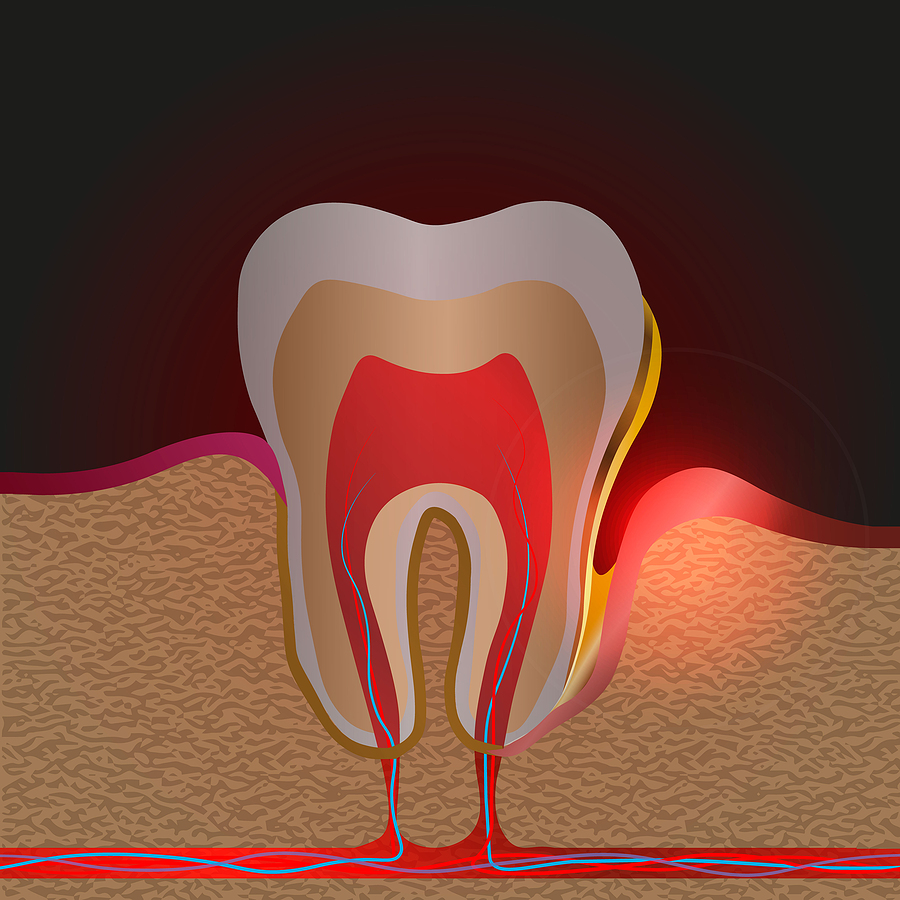

銀歯の下の虫歯は「二次虫歯」と呼ばれます

一度治療した歯が再び虫歯になることを

「二次虫歯(にじむしば)」

と呼びます。

これは

・詰め物や被せ物の隙間

・経年劣化

・接着の弱さ

などが原因で起こります。

理由① 金属は歯に接着していない

銀歯(保険の金属)は、歯と強く接着しているわけではありません。

実は銀歯は

セメントで固定しているだけ

です。

そのため時間が経つと

・セメントが溶ける

・隙間ができる

・細菌が入り込む

という状態が起きることがあります。

この隙間から細菌が侵入すると、銀歯の中で虫歯が進行してしまうのです。

理由④ 銀歯の中で虫歯が進行すると気づきにくい

銀歯の下の虫歯は、外から見えないまま進行することがあります。

そのため

・痛みが出たとき

・レントゲン検査

で初めて発見されることが多いです。

発見された時には

・神経の治療が必要

・歯が大きく崩れている

というケースも少なくありません。